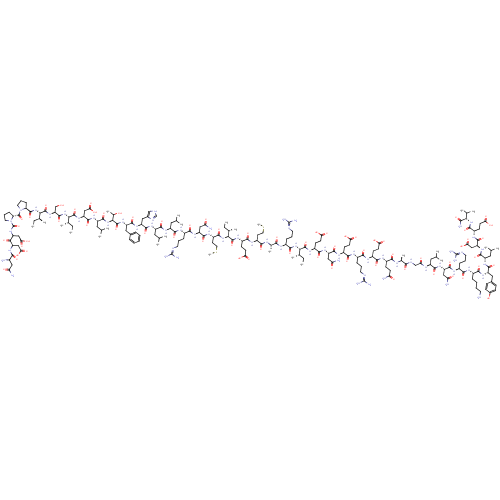

TargetCorticotropin-releasing factor receptor 1(Homo sapiens (Human))

Dupont Pharmaceuticals

Curated by ChEMBL

Dupont Pharmaceuticals

Curated by ChEMBL

Affinity DataEC50: 0.220nMAssay Description:Activity of peptidic agonists on corticotropin releasing factor receptor receptor using agonist-stimulated adenylate cyclase assayMore data for this Ligand-Target Pair